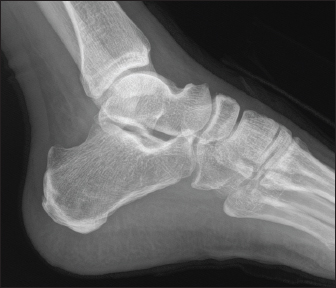

A 70-year-old male known to have diabetes mellitus presented with a 1 month history of fever and weight loss. History of multiple hospital visits and several courses of oral and intravenous antibiotics were present. Physical examination revealed hepatosplenomegaly. As he was fitting the criteria for Pyrexia of Unknown origin, work for the same was done. Routine investigations showed neutrophilic leucocytosis with raised inflammatory markers. Widal was negative. Ultrasound abdomen showed features of chronic liver disease. Contrast CT scan of abdomen showed splenic infarcts. He was started on antibiotics, but he had ongoing fever spikes. While in hospital he developed difficulty in walking due to left ankle pain. MRI foot (Fig. 1) was taken showed small intraosseous abscess in calcaneal bone. Blood cultures grew B. pseudomallei. The patient had a good recovery and was followed up in the outpatient clinic ray foot (Fig. 2) was repeated showed a resolution of osteomyelitis.

Fig. 2. Xray Rt foot after 3 months of treatment—patient 1.